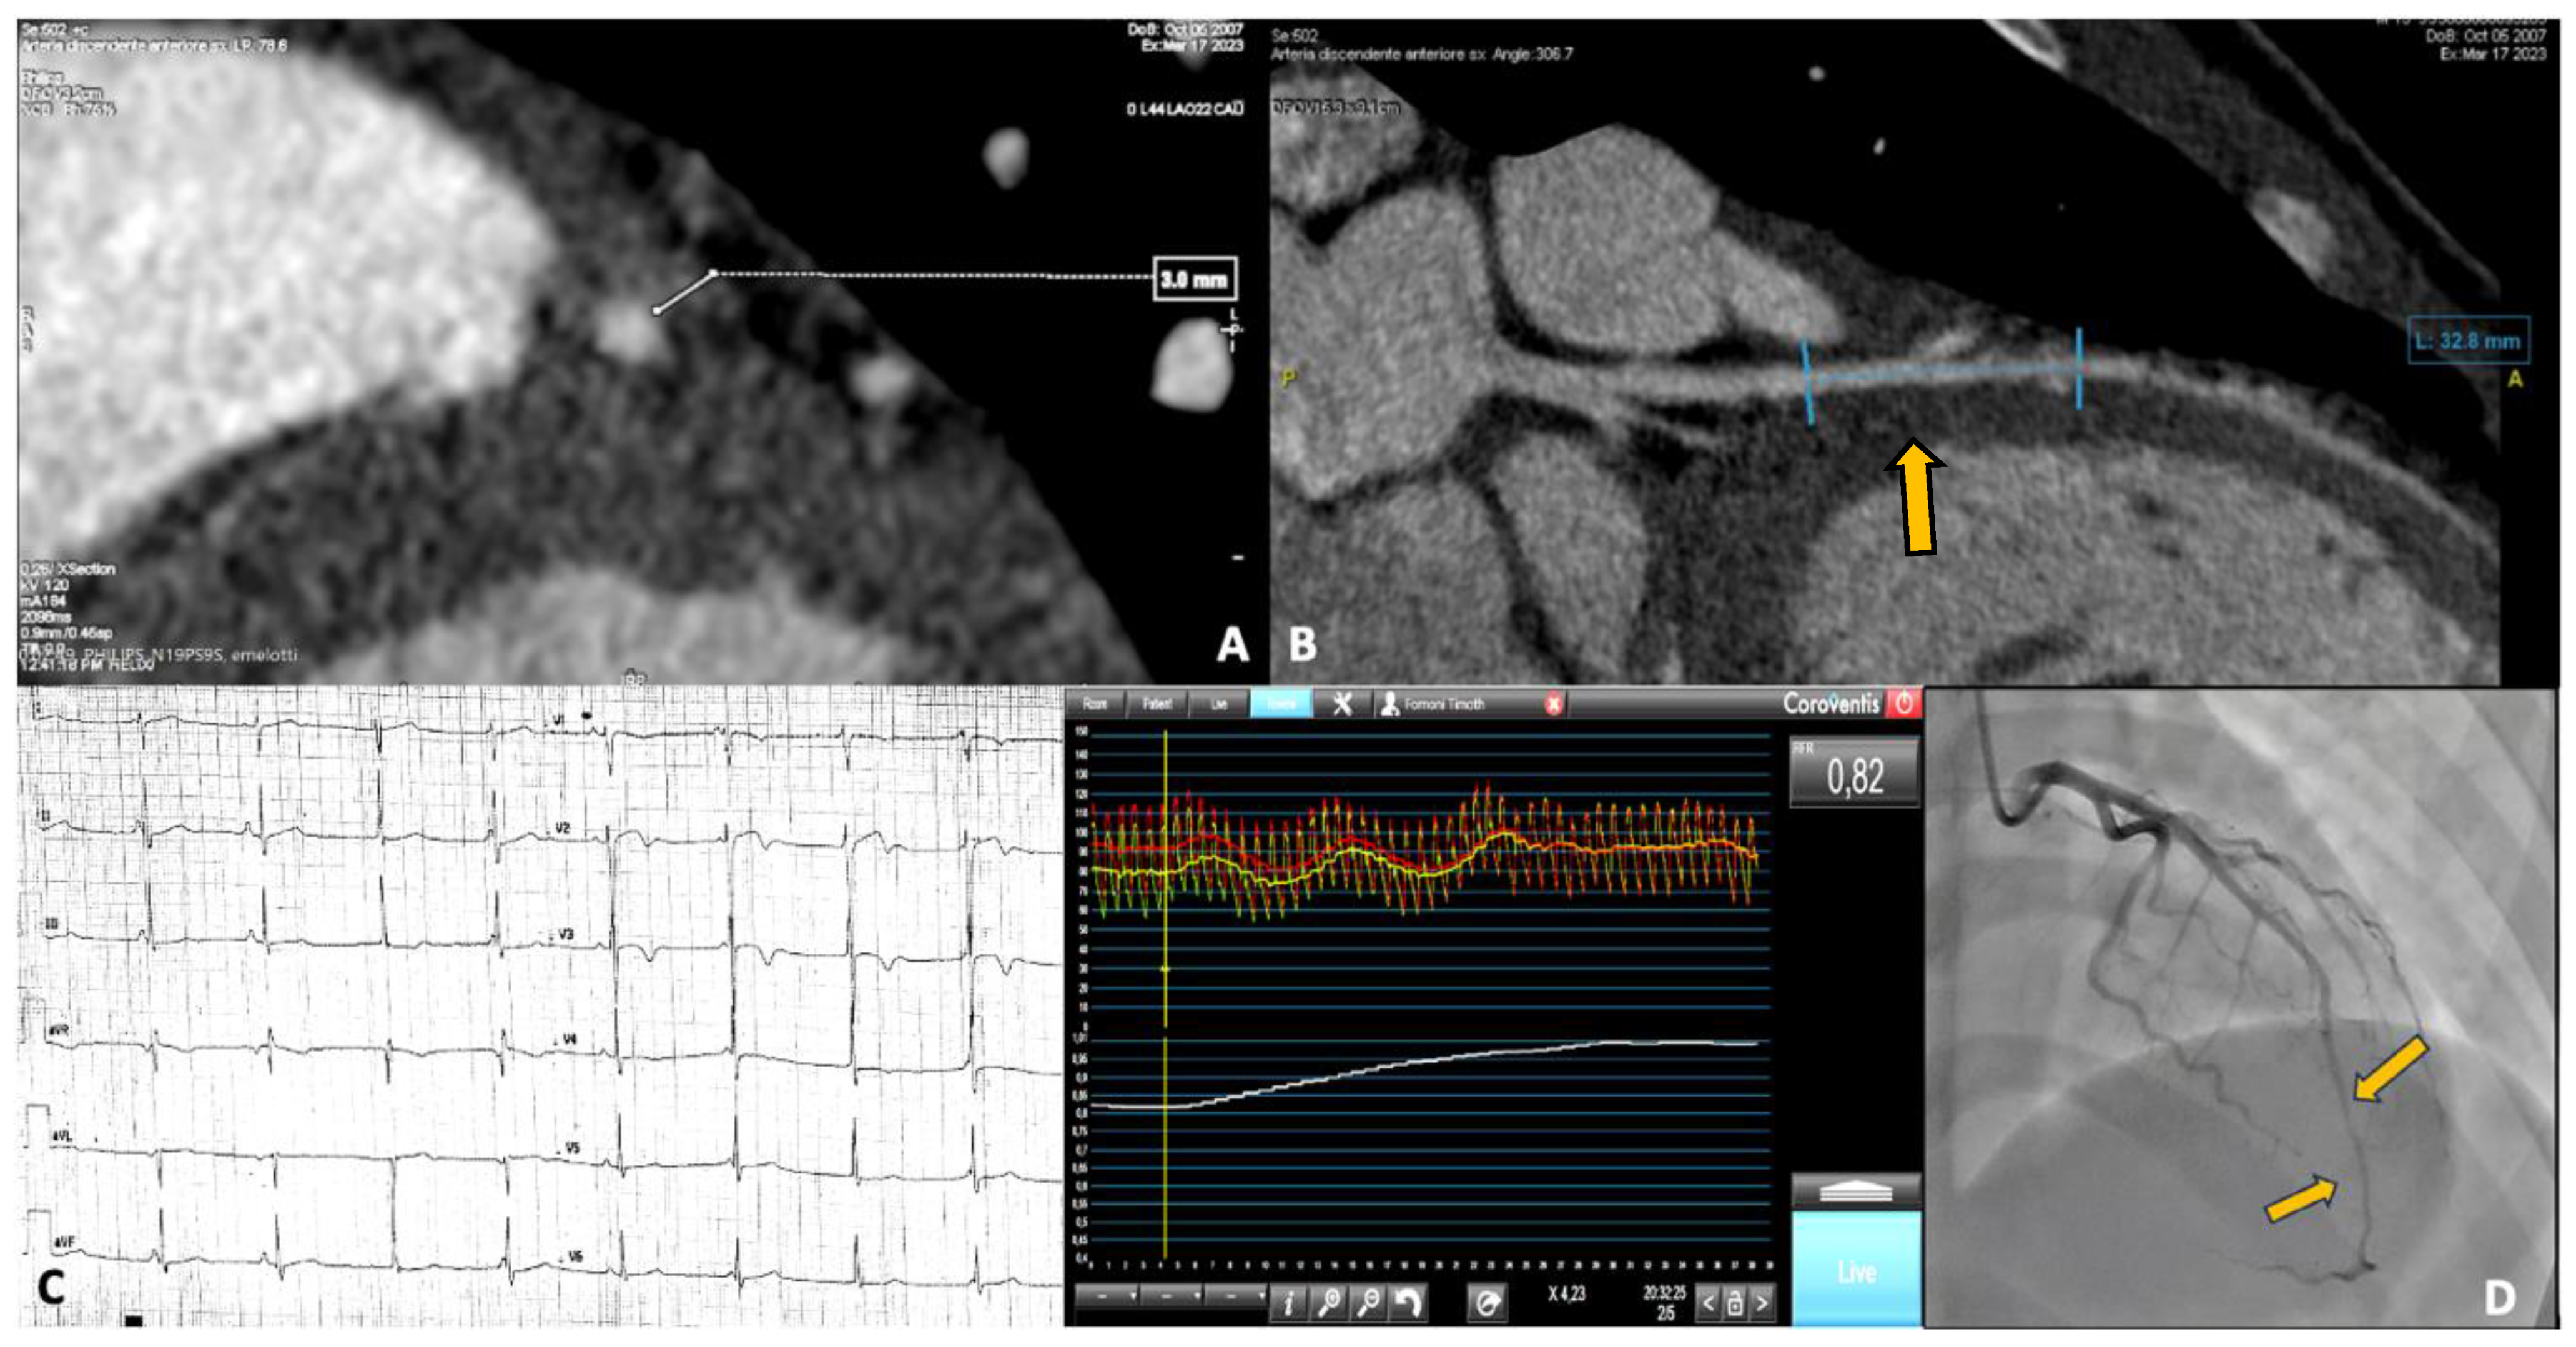

3.2. Case 2: Myocardial Bridge Presented as NSTEMI

| 2 | 15 | Soccer | Myocardial bridge | NSTEMI | Yes |